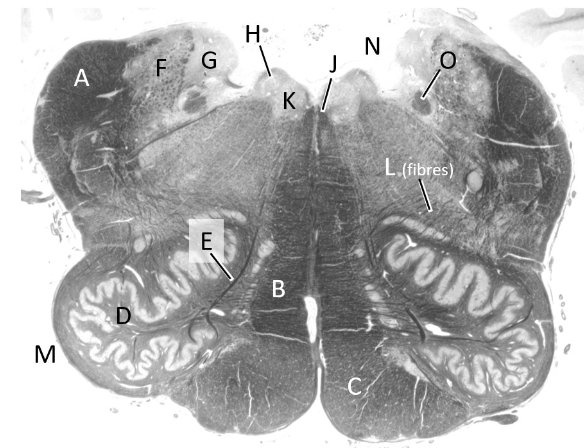

at what level is this?

spino-medullary junction

what is a?

spinal trigeminal nucleus

what is b?

nucleus cuneatus (sm)

what is c?

fasciculus gracilis (sm)

what is e?

pyramidal decussation

what is f?

spinocerebellar & (more medial) spinothalamic tract